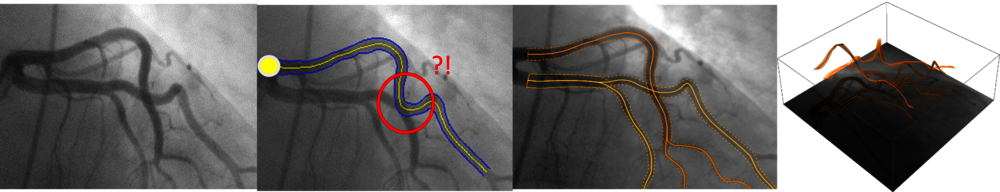

Veel medische en industriële afbeeldingen worden met computers beoordeeld, maar de huidige methodes voor automatische beeldanalyse schieten tekort, vertelt Duits. Zo zijn er problemen met het identificeren en volgen van langgerekte structuren. In medische afbeeldingen zijn dat bijvoorbeeld bloedvaten en vezels; bij industriële afbeeldingen kun je denken aan scheuren in staal of overlappende componenten in beelden van computerchips. “Deze beelden bevatten vaak ruis, wat de interpretatie bemoeilijkt”, legt hij uit. “Bovendien zijn langgerekte structuren vaak complex en lopen ze op de foto’s over elkaar heen. Computers kunnen dan niet altijd goed bepalen wanneer bijvoorbeeld twee bloedvaten elkaar kruisen en wanneer ze vertakken.”

Ter demonstratie toont hij een röntgen-afbeelding van kransslagaders (zie hieronder) waarop vaatbomen te zien zijn. In de rode cirkel zie je verschillende bloedvaten over elkaar heen lopen. “Met het blote oog kun je zien waar de bloedvaten elkaar kruisen, maar de AI kan het zo interpreteren dat het bloedvat daar een afslag neemt.” Het juist segmenteren en volgen van bloedvaten in medische beelden is belangrijk bijvoorbeeld bij de vroege diagnose van diabetes. Maar ook wanneer een katheter bij een patiënt moet worden ingebracht moet de arts deze goed door de aders kunnen navigeren aan de hand van de medische beelden. Een verkeerde interpretatie van het beeld, vaak op de kruising, kan ertoe leiden dat de tracker een verkeerde afslag neemt. Het is dus van essentieel belang om een methode te ontwikkelen die de bloedvaten automatisch volgt met correcte output, zonder last te hebben van kruisingen of ruis.

Duits werkt aan het ontwikkelen van betrouwbare AI-methodes voor beeldanalyse waarmee interpretatiefouten voorkomen kunnen worden. “Met deep learning kan een model aan de hand van data getraind worden om de bloedvaten te identificeren. Maar daarvoor heb je heel veel data van goede kwaliteit nodig, die niet altijd voorhanden zijn, en het verwerken van deze data vraagt veel rekenkracht”, legt hij uit. Net als Schilders is Duits ervan overtuigd dat je wiskunde nodig hebt om te begrijpen wat er in de neurale netwerken precies gebeurt. En als je eenmaal begrijpt hoe het werkt, dan kun je met wiskundige methodes betere neurale netwerken ontwerpen die ook breder toepasbaar zijn in zowel de medische als industriële beeldanalyse.